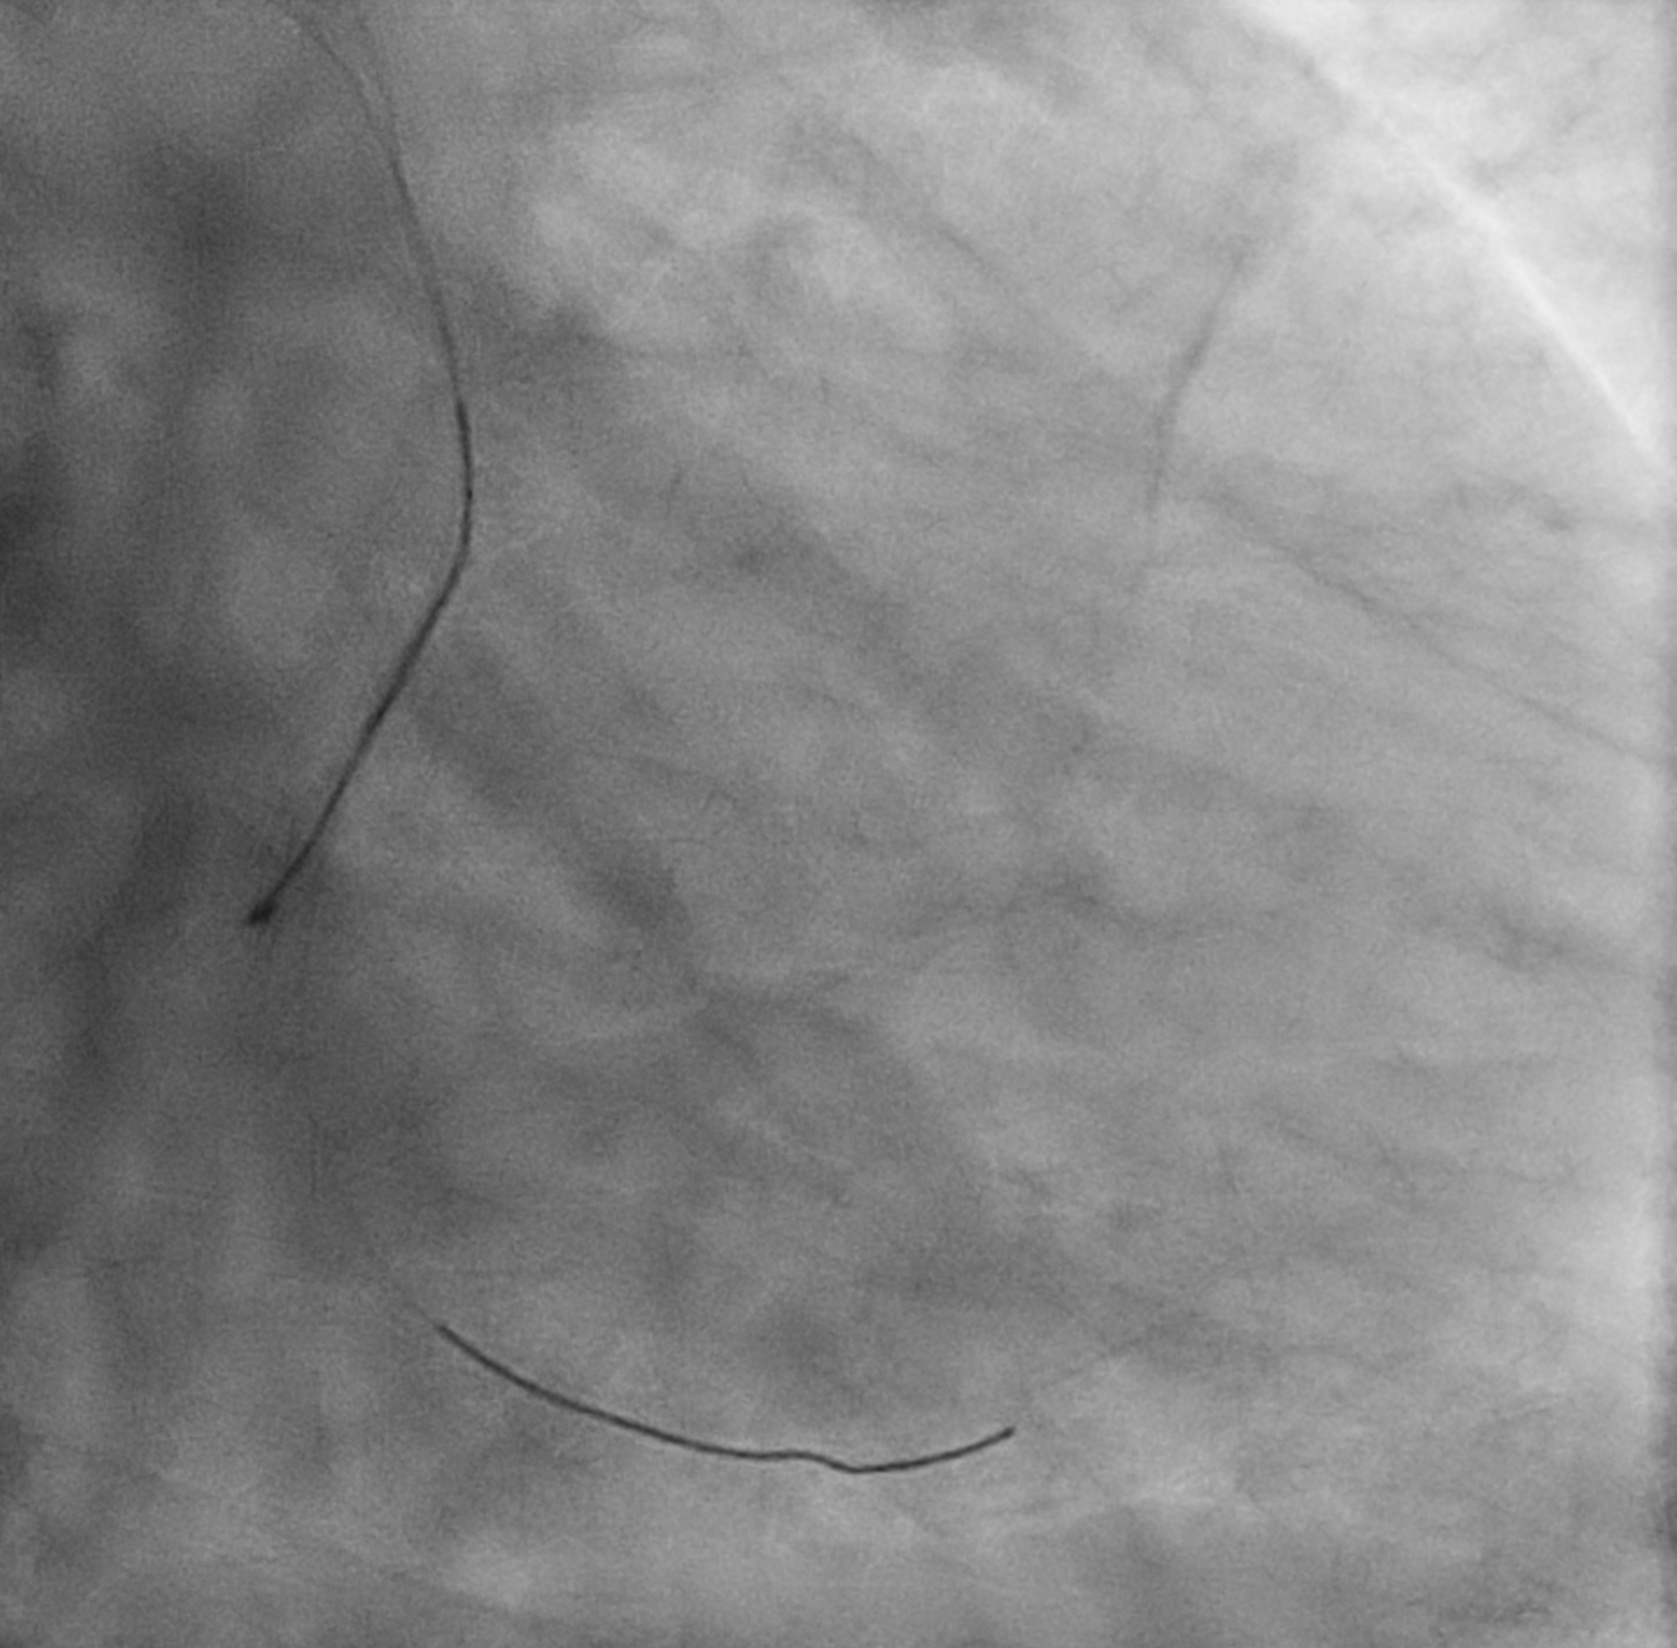

On removal of the knuckled runthrough NS, it was stucked in ventricular branch. Cine confirmed coronary guidewire knot was formed.

Attempted removal with caravel but failed.Attempted wiring to ventricular branch for ballooning but failed.

Finally trapped knotted guidewire was removed with Turnpike.

On removal of the knuckled runthrough NS, it was stucked in ventricular branch. Cine confirmed coronary guidewire knot was formed.

Attempted removal with caravel but failed.Attempted wiring to ventricular branch for ballooning but failed.

Finally trapped knotted guidewire was removed with Turnpike.